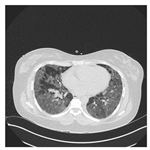

To address contrast-related issues, such as noise and grayscale inhomogeneity commonly observed in CT-scans, the Contrast Limited Adaptive Histogram Equalization (CLAHE) [] method is implemented following the data-scaling step. CLAHE is specifically utilized to alleviate these problems and enhance the visualization of CT-scans. By applying the CLAHE method, image noise is effectively reduced, while simultaneously generating pixels with improved grayscale contrast []. Consequently, CT-scans become more visually discernible, aiding in the accurate analysis and interpretation of the images. A comparative illustration of CT-scan samples before and after the application of the CLAHE method is presented in Table 4 [], highlighting the significant enhancement achieved through this preprocessing technique.

Table 4.

CT-scan comparison before and after CLAHE application [].